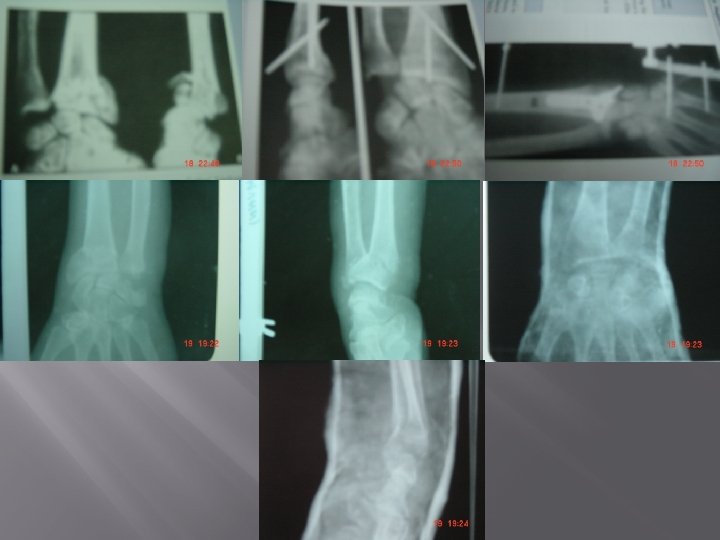

SMITH FRACTURE / REVERSE COLLE'S FRACTURE � � Definition: Fracture of distal one third of radius with palmar or volar displacement. Mechanism of injury: a) Fall on back of dorsum of hand b) Fall on forearm in supination c) Direct blow on flexed hand. Clinical Features: Pain, swelling Deformity Garden Spade deformity. Loss of wrist functions. Radiology: X-ray wrist– AP view – Lateral view – Carpus displaced proximally – Fracture fragment displaced anteriorly with palmar angulation.

� � • Conservative Treatment: Reduction setting, above elbow POP casts [forearm in supination, wrist in extension]. Surgical: For unstable fractures – open/close reduction and fixation by K-wire, plate or screws. Complication: Usually arises due to misdiagnosis as Colle's other complications are similar to Colle's.

BARTON FRACTURE � � Definition: It is an intrarticular fracture dislocation or subluxation in which rim of distal radius is displaced either dorsally or volarly along with carpal bones. Dislocation is most clinically and radiographically obvious abnormality. Dorsal Barton Volar Barton Type Posterior marginal type Anterior marginal type Variant of Colle's Variant of Smith Mechanis m Fall with dorsiflexion & pronation of distal forearm on a flexed wrist. Below elbow POP with wrist in neutral position. Due to palmar tensile stress or dorsal shear stress. Above elbow POP after reduction. Percutaneous K-wire fixation. External fixation. Treatment Operative